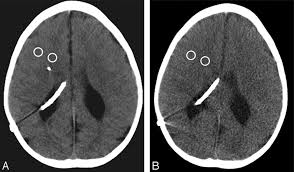

Radiological Findings Before And After Vp Shunt Placement Notes A Download Scientific Diagram